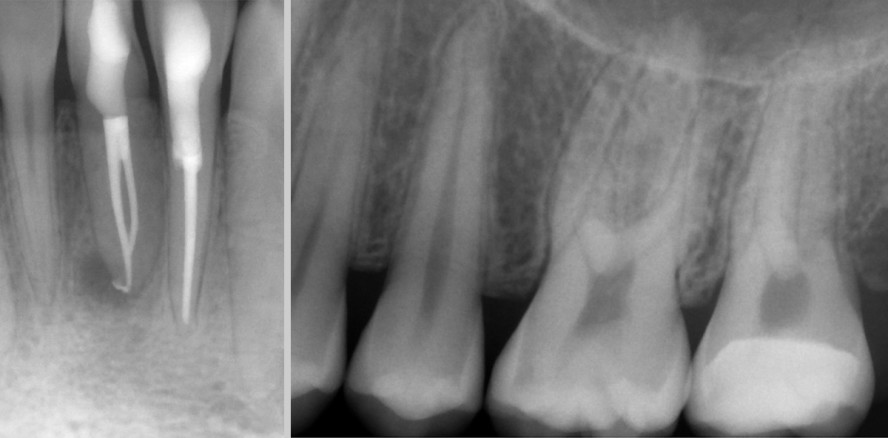

Beim periapikalen Röntgenbild erfolgt eine Komprimierung des dreidimensionalen Objekts auf ein zweidimensionales Bild, auf welchem der Betrachter gedanklich die dritte Dimension wieder herstellen muss. Bukkal und oral befindliche Strukturen überlagern das eigentliche Objekt und verändern dadurch die Aussagekraft des Bildes. Der Kontrast zwischen der Läsion und seiner Umgebung ist nicht eindeutig erkennbar (Abb. 1 und 2).2,15

Aufgrund dessen kann beim konventionellen Röntgenbild eine apikale Läsion nicht eindeutig diagnostiziert werden. Dies gilt sowohl bei der präoperativen Diagnostik als auch bei der Verlaufskontrolle und den damit verbundenen Erfolgsstatistiken. Hier ist das DVT der Zahnfilmaufnahme signifikant überlegen, was in zahlreichen Studien bestätigt wurde.7,9,13,15,19 Die Beurteilung der periapikalen Region ist aber für die Diagnose und die Therapie bei endodontischen Eingriffen von entscheidender Bedeutung.